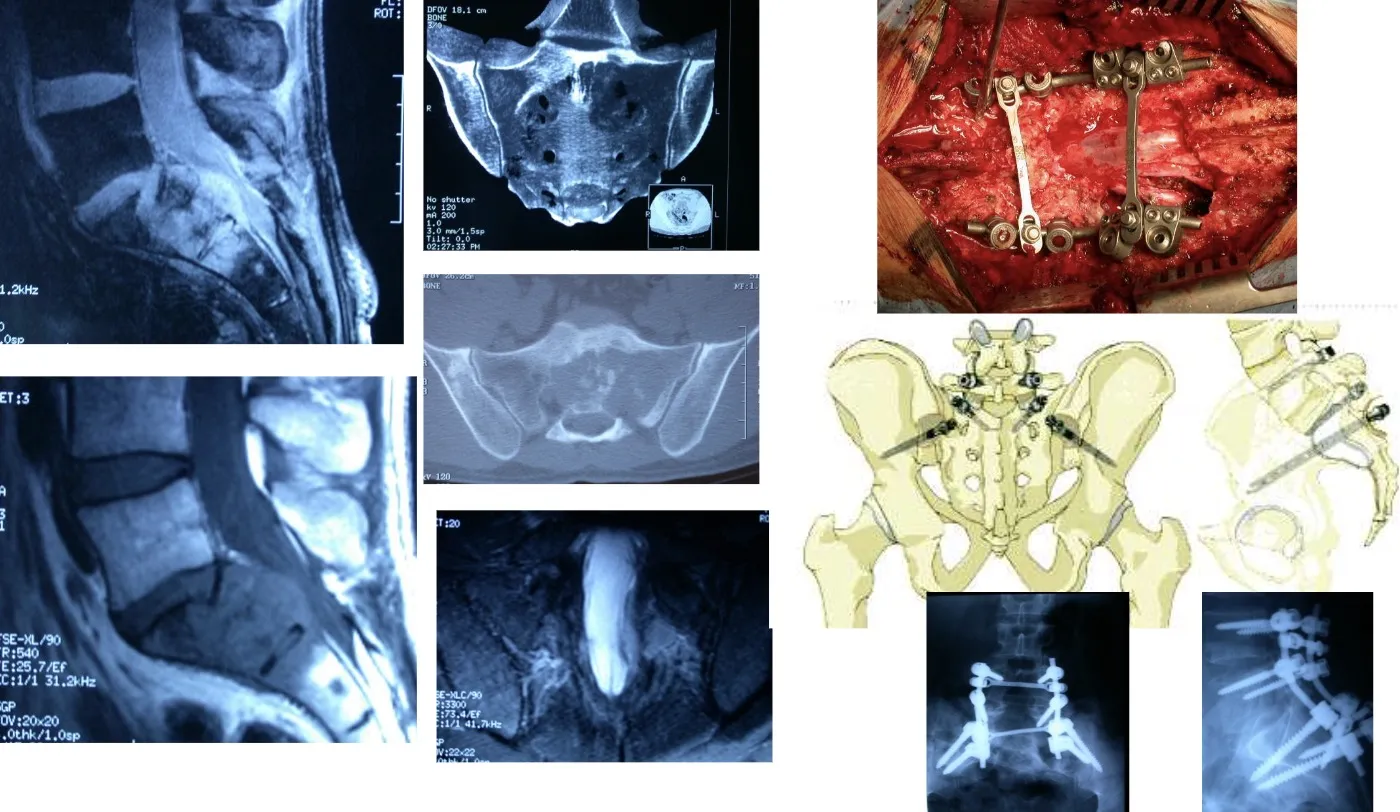

Otro tumor maligno es el Cordoma, que se localiza con mayor frecuencia en el sacro. Su tratamiento representa un reto quirúrgico de gran complejidad, ya que suele implicar estructuras anatómicas críticas y requiere una resección amplia y precisa para lograr un buen control local de la enfermedad.

Este es un ejemplo de las intervenciones de gran envergadura que en ocasiones es necesario realizar, como en el caso de las cirugías de la región sacra, donde la complejidad anatómica y la proximidad de estructuras vitales exigen una planificación meticulosa y un abordaje multidisciplinario.

En el caso de la transición entre la columna torácica y la lumbar, la cirugía resulta especialmente compleja debido a la presencia del diafragma y a las particularidades anatómicas de esta región. En estas situaciones pueden ser necesarios abordajes combinados o específicos, que permitan acceder tanto por vía anterior como posterior. A menudo es preciso reconstruir el soporte anterior de la columna mediante injertos o prótesis para restaurar la estabilidad y garantizar que la columna se mantenga firme y alineada tras la intervención.

Hoy en día disponemos de la capacidad técnica y humana, gracias a la colaboración con otros especialistas, para llevar a cabo grandes intervenciones quirúrgicas en la columna lumbar, procedimientos que hace apenas unos años presentaban una morbilidad tan elevada que los hacía desaconsejables tanto para los cirujanos como para los propios pacientes.

El abordaje de estos casos debe realizarse siempre dentro de un equipo multidisciplinario, que analice la situación de forma conjunta antes de iniciar cualquier tratamiento. Es fundamental valorar la morbilidad esperada, que puede ser mínima o significativa dependiendo de los recursos disponibles, la experiencia del equipo y las características concretas del tumor. También hay que determinar el tipo de cirugía más adecuado: en muchos casos basta con una resección intralesional, como ocurre habitualmente en Neurocirugía, mientras que en otros puede ser necesario recurrir a procedimientos más agresivos, como la resección en bloque de la vértebra afectada, para lograr un control oncológico adecuado.